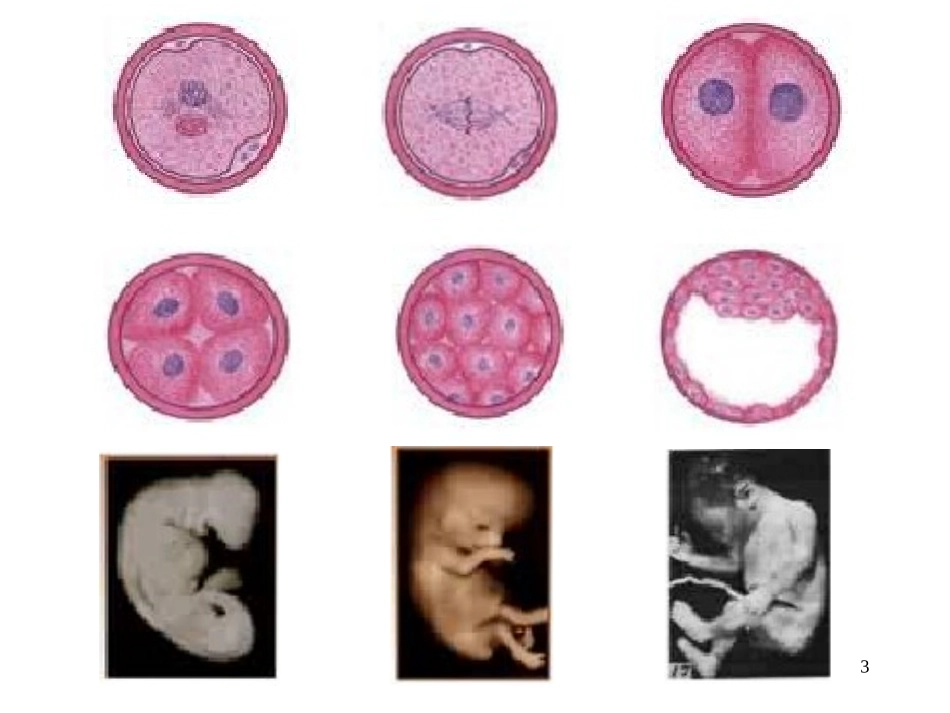

1广东医学院病理生理学教研室2受精卵成人200多种细胞约1014个细胞1个细胞“细胞增殖”“细胞分化”34受精卵成人200多种细胞约1014个细胞1个细胞“细胞增殖”“细胞分化”“细胞凋亡”5细胞增殖的概述细胞增殖异常与疾病细胞周期及其调控细胞周期调控异常与疾病调控细胞周期与疾病的防治6细胞增殖(cellproliferation)细胞分化(celldifferentiation)细胞通过生长和分裂使细胞数目增加,使子细胞获得和母细胞相同遗传特性的过程。细胞通过分裂增殖产生结构和功能上有特定差异的子代细胞的过程。两者关系:相互关联但有所不同两者关系:相互关联但有所不同基因型相同基因型相同细胞表型不同概述概述7•生命延续的保证•生长发育的基础•维持细胞数量稳态细胞增殖分化生物学意义概述概述•参与创伤修复8细...